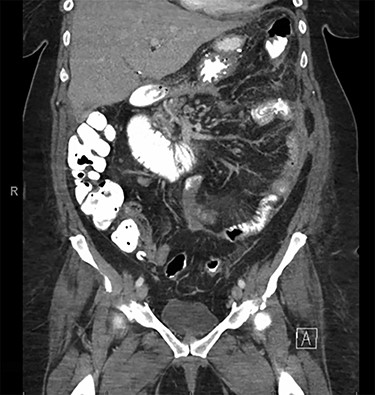

Decision was made to explore and attempt to excise the infarcted omentum. She was taken to the operating room and underwent a diagnostic laparoscopy. However, due to the large size of the omental infarction with an encapsulated necrotic liquefied, purulent secretion and significant adhesions, we decided to convert it to a midline laparotomy. We then proceeded with resection of right-sided infarcted, necrotic, liquefied omentum and abdominal washout (Fig. 3). Culture from the purulent secretion that was inside encapsulated omentum grew Streptococcus anginosus. She received Meropenem and Fluconazole. She had a prolonged and protracted recovery with a transient kidney injury and the development of multiple intra-abdominal (inter-loop, peri-hepatic, peri-splenic and pelvic) fluid collections (Fig. 4A). These collections were treated by percutaneous drainage (pelvis × 1, perisplenic and left-sided collections × 2). Three weeks from the take back, she developed a small bowel obstruction with significant dilation of the biliopancreatic limb and excluded stomach (Fig. 4B and C). She was taken to the operating room and had an endoscopically placed nasogastric tube just passed the jejunojejunostomy. Then, she underwent CT-guided gastrostomy tube to decompress in the gastric remnant (Fig. 5 A and B). One week after the rendezvous nasogastric and gastric remnant decompression, an oral and through the G-tube contrast study demonstrated patency of the gastrojejunostomy and resolution of the small bowel obstruction (Fig. 6). The patient was discharged home on POD #39 tolerating a regular postbariatric surgery diet.

Follow-up abdominal and pelvic CT scan at POD # 35 with interval resolution of intra-abdominal abscess and small bowel obstruction.